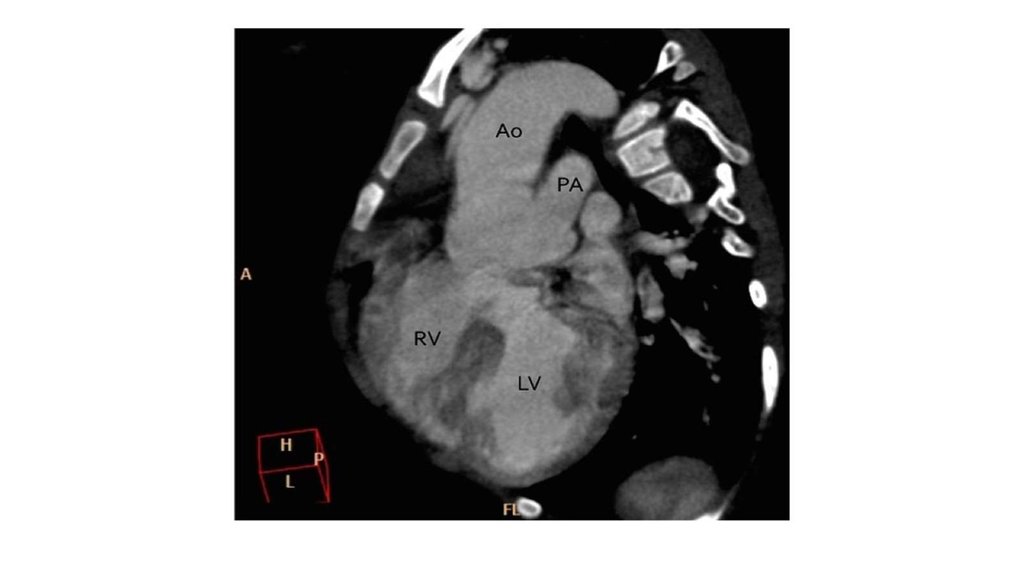

Общий артериальный ствол